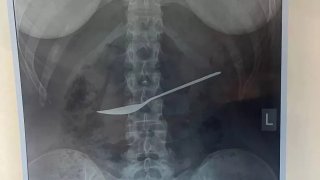

หมอช็อก!! หลังเจอช้อนทั้งด้าม ในท้องเด็ก

แพทย์จากโรงพยาบาลคลินิกภูมิภาค รัฐโวล็อกดา ในประเทศรัสเซีย ได้ทำการรักษาเด็กหญิงคนหนึ่ง ที่ร้องบ่นเรื่องปวดท้องอยู่ซ้ำๆ อย่างไม่ทราบสาเหตุ หลังจากทำการเอ็กซเรย์หลายครั้ง เพื่อพยายามค้นหาสาเหตุของความเจ็บปวด ในที่สุดแพทย์ก็พบว่าสิ่งแปลกปลอมในท้อง คือ ช้อนโลหะทั้งด้าม ซึ่งมีความยาวประมาณ 8 นิ้ว" แพทย์กล่าวว่า "เธอน่าจะกลืนเข้าไป ขณะกินอาหารกลางวัน" และ "เราได้ทำการส่องกล้องทางหลอดอาหาร เนื่องจากเด็.. ดูเพิ่ม